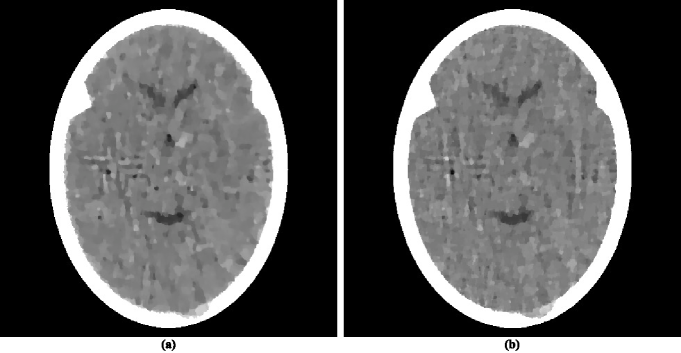

There have appeared in the literature some approaches to TV𝑇𝑉TV minimization that seem to indicate a more efficacious performance for CT than the one reported in HERM08a (31). One of these is the Adaptive Steepest Descent Projections Onto Convex Sets (ASD-POCS) algorithm, which is described in detail in the much-cited paper of Sidky and PanSIDK08a (42) and whose use has been since reported in a number of subsequent publications, for example, in SIDK11a (23, 43). We note that ASD-POCS was designed with the aim of producing an exact minimization algorithm, in contrast to our heuristic superiorization approach. Translating equations (6)-(8) of SIDK08a (42) into our terminology, the aim of ASD-POCS is the following: Given an ε+𝜀subscript\varepsilon\in\mathbb{R}_{+}, find an ε𝜀\varepsilon-compatible 𝒙Ω=+J𝒙Ωsuperscriptsubscript𝐽\boldsymbol{x}\in\Omega=\mathbb{R}_{+}^{J} for which TV(𝒙)𝑇𝑉𝒙TV(\boldsymbol{x}) is minimal. (Note that this aim is a special case of the constrained optimization formulation presented in (10).) In order to test ASD-POCS, we generated realistic projection data as described in the previous subsection but for only 60 views at 3 degree increments with the spacing between the lines for which integrals are estimated set at 0.752 mm. Thus the number of rays (and hence the number photons put into the head) in this data set is a twelfth of what it is in the data set used to produce the reconstruction in figure 1(b). A reconstruction from these data was produced for us using ASD-POCS by the authors of SIDK08a (42) (this ensured that it does not suffer due to our misinterpretation of the algorithm or from our inappropriate choices of the free parameters), it is shown in figure 2(a).

Refer to caption

Figure 2: Reconstructions using TV𝑇𝑉TV as the optimization criterion from realistically simulated projection data for 60 views using (a) ASD-POCS and (b) superiorization. As compared to figure 1(b), these reconstructions fail in two ways: they do not show some of the fine details in the phantom and they present some artifactual variations. The former of these is a consequence of reconstructing from a much smaller data set than used for figure 1(b). The latter is due to using a very narrow window (13.5 HU) in these displays. Were we to use a wider display window (e.g., from -429 HU to 429 HU) for the reconstructions in this figure and in figure 1(b), the visual appearance of the resulting images would be nearly indistinguishable.

Since the image quality of figure 2(a) is not anywhere near to that of figure 1(b), we present here a brief discussion as to why we are showing such images. Many publications in the recent medical imaging literature have claimed that medically-efficacious reconstructions can be obtained by the use of TV𝑇𝑉TV-minimization from data as sparse as what was used to produce figure 2(a). (In fact, ASD-POCS was motivated and used with such an aim in mindSIDK11a (23, 42, 43).) Such publications usually show reconstructions from sparse data as evidence for the validity of their claims. They can do this because in their presented illustrations the features that are observable in the reconstructions are usually much larger and/or of much higher contrast against their backgrounds than the small “tumors” in figure 1(a), which are perfectly visible in the reconstruction in figure 1(b), but are not detectable in the reconstruction from sparse data in figure 2(a). The reason why that reconstruction appears to be unacceptably bad is that the display window (from 0.204 cm-1 linear attenuation coefficient to 0.21675 cm-1 linear attenuation coefficient) is very narrow; it was selected to enhance the visibility of the small low-contrast tumors. The width of this window corresponds to about 13.5 Hounsfield Units (HU). As compared to this, in their evaluation of sparse-view reconstruction from flat-panel-detector cone-beam CT, Bian et al.BIAN10A (43) use what they call a “soft-tissue grayscale window” (also a “narrow window”) from -429 HU to 429 HU to display head phantom reconstructions. Using such a window for our reconstructions shown figures 2(a) and 1(b) would result in images that are nearly indistinguishable from each other. Thus reporting the images using such a display window is consistent with the claim that a TV-minimizing reconstruction from a few views is similar in quality to a more traditional reconstruction from many views. However, our much narrower display window reveals that this is not really so. We therefore continue using our much narrower window in what follows, since it clearly reveals the nature of the reconstructions being compared, warts and all.

While this ASD-POCS reconstruction is not as good as it should be for diagnostic CT of the brain (due to the sparsity of the data), it is visually better than the reconstruction using superiorization from similar data as reported inHERM08a (31). We discuss the reasons for this in the next subsection. Here we concentrate on examining whether one can achieve a reconstruction using superiorization that is as good as that produced by ASD-POCS from the same data.

For this we first need to examine the numerical properties of the ASD-POCS reconstruction. This reconstruction uses 485×485485485485\times 485 pixels each of size 0.376 mm by 0.376 mm. This implies that J=235,225𝐽235225J=235,225 and it also determines the components of the vectors 𝒂iJsuperscript𝒂𝑖superscript𝐽\boldsymbol{a}^{i}\in\mathbb{R}^{J} in the precise specification of the problem S𝑆S. The ResS𝑅𝑒subscript𝑠𝑆Res_{S}, as defined by (2), of the ASD-POCS reconstruction is 0.33 and the TV𝑇𝑉TV, as defined by (12), is 835.

We applied to the same problem S𝑆S a superiorized version of the algorithm 𝐑𝐑\mathbf{R} defined by (3). To complete the specification of 𝐑𝐑\mathbf{R}, we point out that for the ordering of views we chose the “efficient” one that was introduced in HERM93a (58) and is also discussed on page 209 of HERM09a (55). The choices we made for the superiorization are the following: γ=0.99995subscript𝛾superscript0.99995\gamma_{\ell}=0.99995^{\ell}, 𝒙¯bold-¯𝒙\boldsymbol{\bar{x}} is the zero vector and N=20𝑁20N=20. The nonascending vector was computed by the method described in the paragraph below (12). Denoting by RSsubscript𝑅𝑆R_{S} the infinite sequence of points in ΩΩ\Omega that is produced by the superiorized version of the algorithm 𝐑𝐑\mathbf{R} when applied to the problem S𝑆S, we chose as our reconstruction 𝒙=O(S,0.33,RS)superscript𝒙𝑂𝑆0.33subscript𝑅𝑆\boldsymbol{x^{*}}=O\left(S,0.33,R_{S}\right). For such a reconstruction we have, by the definition of O𝑂O, that ResS(𝒙)0.33𝑅𝑒subscript𝑠𝑆superscript𝒙0.33Res_{S}\left(\boldsymbol{x^{*}}\right)\leq 0.33; in other words, the output of the superiorization algorithm is at least as constraints-compatible with S𝑆S as the output of ASD-POCS. From the point of view of TV𝑇𝑉TV-minimization, our 𝒙superscript𝒙\boldsymbol{x^{*}} is slightly better: TV(𝒙)=𝑇𝑉superscript𝒙absentTV\left(\boldsymbol{x^{*}}\right)=826.

The superiorization reconstruction is displayed in figure 2(b). Visually it is similar to the reconstruction produced by ASD-POCS. From the optimization point of view it achieves the desired aim better than ASD-POCS does, since it results in smaller values for both ResS𝑅𝑒subscript𝑠𝑆Res_{S} and for TV𝑇𝑉TV, even though only slightly.

That the two reconstructions in figure 2 are very similar is not surprising because a comparison of the pseudo-codes reveals that the ASD-POCS algorithm in SIDK08a (42) is essentially a special case of the Superiorized Version of Algorithm 𝐏𝐏\mathbf{P}, even though it has been derived from rather different principles. To obtain the ASD-POCS algorithm from our methodology described here, we would have to choose an Algebraic Reconstruction Technique (ART; see Chapter 11 of HERM09a (55)) as the algorithm that we are superiorizing. Such a superiorization of ART was reported in the earliest paper on superiorization BUTN07a (27). For the illustration in our current paper we decided to superiorize the block-iterative algorithm 𝐑𝐑\mathbf{R} defined by (3). This illustrates the generality of the superiorization approach: it is applicable not only to a large class of constrained optimization problems, but also enables the use of any of a large class of iterative algorithms designed to produce a constraints-compatible solutions. A recent publication aimed at producing an exact TV𝑇𝑉TV-minimizing algorithm based on the block-iterative approach is DEFR11a (44).

III.4 Effects of variations in the reconstruction approach

The reconstruction in figure 2(a) produced by ASD-POCS definitely “looks better” than a reconstruction in HERM08a (31), which was obtained using superiorization from similar data. Since, as discussed in the last paragraph of the previous subsection, the ASD-POCS algorithm in SIDK08a (42) can be obtained as a special case of superiorization, it must be that some of the choices made in the details of the implementations are responsible for the visual differences. An analysis of the implementational details adopted by the two approaches revealed several differences. After removing these differences, the superiorization approach produced the image in figure 2(b), which is very similar to the reconstruction produced by ASD-POCS. We now list the implementational choices that were made for superiorization to make its performance match that of the reported implementation of ASD-POCS.

One implementational difference is in the stopping-rule of the iterative algorithm; that is, the choice of ε𝜀\varepsilon in determining the output O(S,ε,RS)𝑂𝑆𝜀subscript𝑅𝑆O\left(S,\varepsilon,R_{S}\right). Since the data are noisy, the phantom itself does not match the data exactly. In previously reported implementations of superiorization it was assumed that the iterative process should terminate when an image is obtained that is approximately as constraints-compatible as the phantom; in the case of the phantom and the projections data on which we report here the value of ResS𝑅𝑒subscript𝑠𝑆Res_{S} for the phantom is approximately 0.91, which is larger than its value (0.33) for the reconstruction produced by ASD-POCS. The output O(S,0.91,RS)𝑂𝑆0.91subscript𝑅𝑆O\left(S,0.91,R_{S}\right) is shown in figure 3(a). This is a wonderfully smooth reconstruction, its TV𝑇𝑉TV value is only 771. However this smoothness comes at a price: we loose not only the ability to detect the large tumor, but we cannot even see anatomic features (such as the ventricular cavities) inside the brain. So it appears that, in order to see medically-relevant features in the brain, over-fitting (in the sense of producing a reconstruction from noisy data that is more constraints-compatible than the phantom) is desirable.

Figure 3: Reconstructions produced by varying some of the parameters in the algorithm that produced figure 2(b). (a) Changing the termination criterion form ε=0.33𝜀0.33\varepsilon=0.33 to ε=0.91.𝜀0.91\varepsilon=0.91. (b) Changing the value of N𝑁N from 20 to 1. (c) Reconstructing with pixel size 0.752 mm by 0.752 mm instead of 0.376 mm by 0.376 mm. (d) Reconstructing with all the three changes of (a)-(c).

In the implementations that produced previously reported reconstructions by superiorization, the number N𝑁N in the Superiorized Version of Algorithm 𝐏𝐏\mathbf{P} was always chosen to be 1. It is possible that this is the wrong choice, making only this change to what lead to the reconstruction in figure 2(b) results in the reconstruction shown in figure 3(b). That image appears similar to the image in figure 2(b), but it has a higher TV𝑇𝑉TV value, namely 832, which is still very slightly lower than that of the ASD-POCS reconstruction. The choice N=20𝑁20N=20 was based on the desire to maintain consistency with what has been practiced using ASD-POCS, see page 4790 of SIDK08a (42). It appears that in the context of our paper the additional computing cost due to choosing N𝑁N to be 20 rather than 1 is not really justified. (We note that if 𝒅𝒅\boldsymbol{d} is selected using subgradients as discussed in the paragraph following (7) and thus 𝒅𝒅\boldsymbol{d} is not guaranteed to be a nonascending vector for the TV𝑇𝑉TV function, then the choice of 20 rather than 1 for N𝑁N results in a considerable improvement. However, an even greater improvement is achieved even with N=1𝑁1N=1 by selecting 𝒅𝒅\boldsymbol{d} as recommended in this paper.)